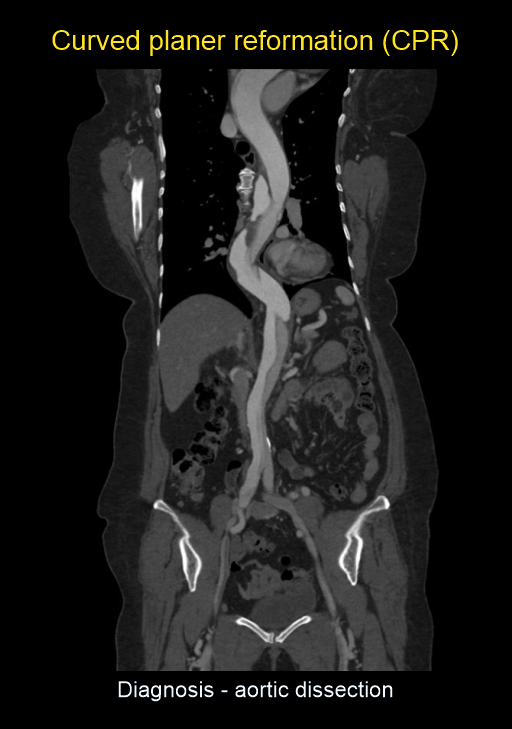

- Curved planar reformation (CPR) images of aorta.